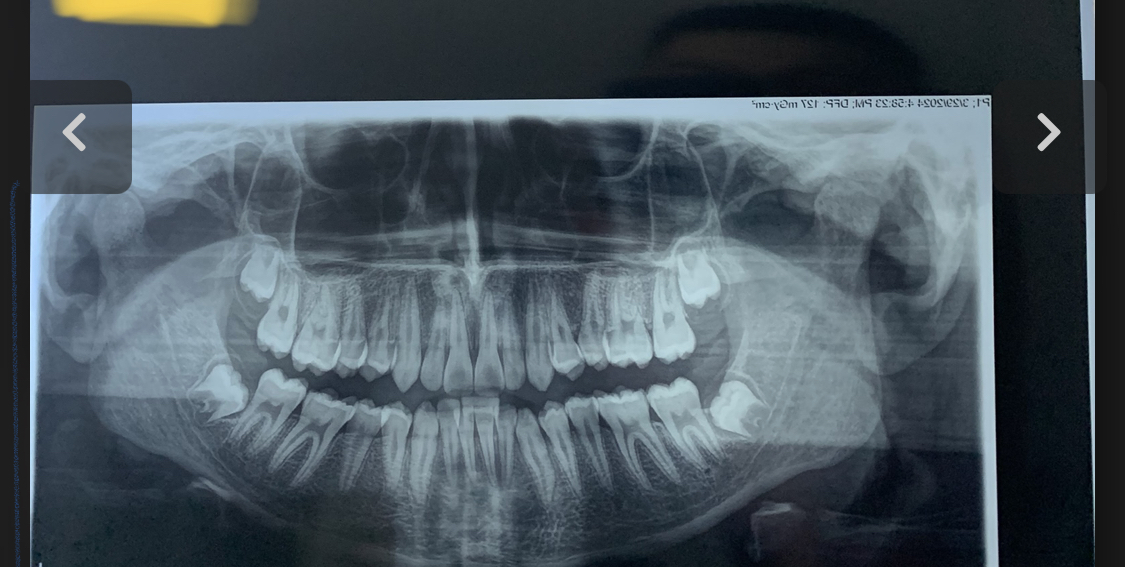

Chewing fr made my mandible longer and wider (the bone).Made my ramus longer and increases my bigonial width.My chin is also more projected.

I chewed on one side a lot more gum and now i see the changes.

I also did mewing in the other side which my jaw is more narrow.My cheekbones are higher set and more prominent.My midface shorter.And better eye hooding and better pfl.

Now im trying to atrophy my masseter muscle since it make me look bloated but the changes on the bone are 100% real.

Im planing on chewing more in the side which my jaw is narrower and mewing more in the side thag my cheekbones are lower.I hope i fix this.